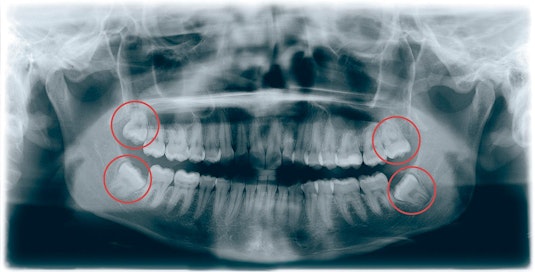

Viisaudenhammas

Viisaudenhampaat ovat jäänne esihistoriasta, jolloin karkea ravinto kulutti hampaita